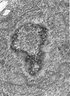

Cells: TEM images